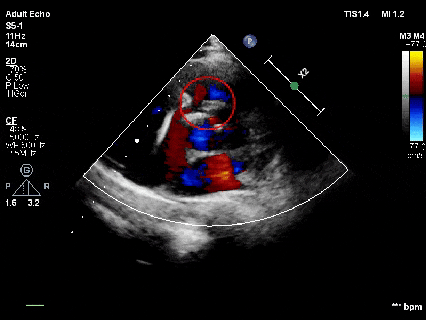

释放后超声

超声下可见室水平和房水平都无残余分流

心脏彩超:心脏超声下可见两个封堵器双盘稳固夹持,无残余分流;

术后1个月心脏超声,房室水平皆无残余分流